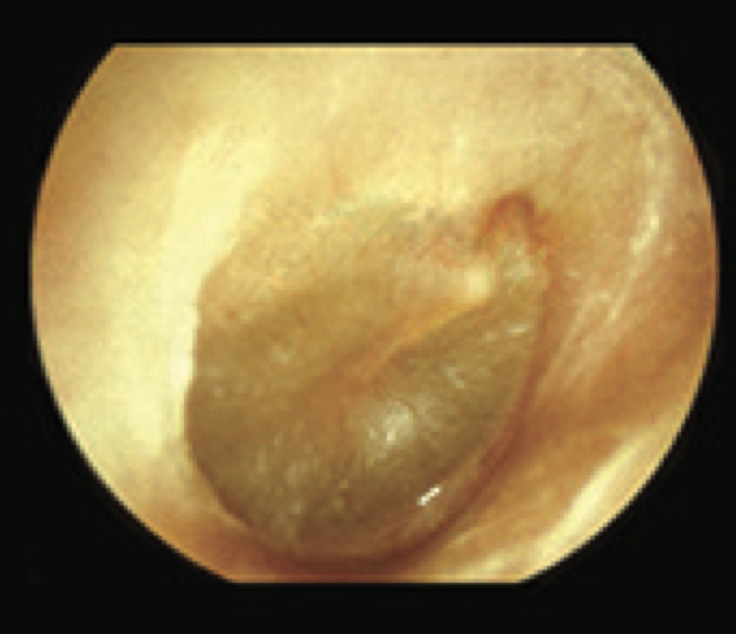

5

Q

What is this?

A

Acute secretory OM I

- Dull TM

- altered light reflex

-blood vessels on surface